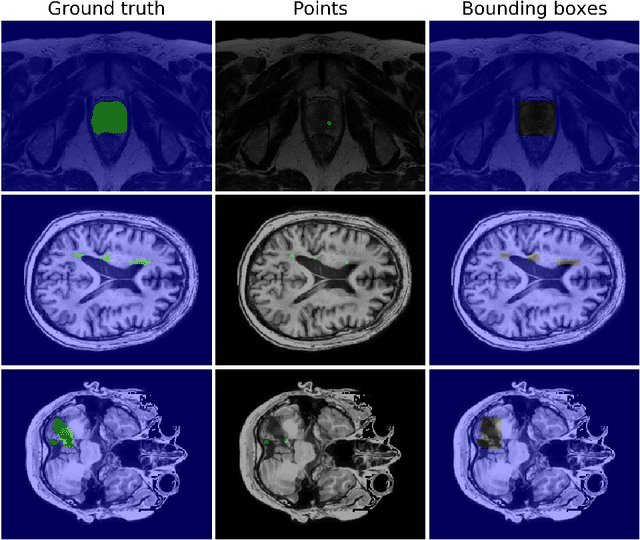

Abstract:We propose a novel weakly supervised learning segmentation based on several global constraints derived from box annotations. Particularly, we leverage a classical tightness prior to a deep learning setting via imposing a set of constraints on the network outputs. Such a powerful topological prior prevents solutions from excessive shrinking by enforcing any horizontal or vertical line within the bounding box to contain, at least, one pixel of the foreground region. Furthermore, we integrate our deep tightness prior with a global background emptiness constraint, guiding training with information outside the bounding box. We demonstrate experimentally that such a global constraint is much more powerful than standard cross-entropy for the background class. Our optimization problem is challenging as it takes the form of a large set of inequality constraints on the outputs of deep networks. We solve it with sequence of unconstrained losses based on a recent powerful extension of the log-barrier method, which is well-known in the context of interior-point methods. This accommodates standard stochastic gradient descent (SGD) for training deep networks, while avoiding computationally expensive and unstable Lagrangian dual steps and projections. Extensive experiments over two different public data sets and applications (prostate and brain lesions) demonstrate that the synergy between our global tightness and emptiness priors yield very competitive performances, approaching full supervision and outperforming significantly DeepCut. Furthermore, our approach removes the need for computationally expensive proposal generation. Our code is shared anonymously.